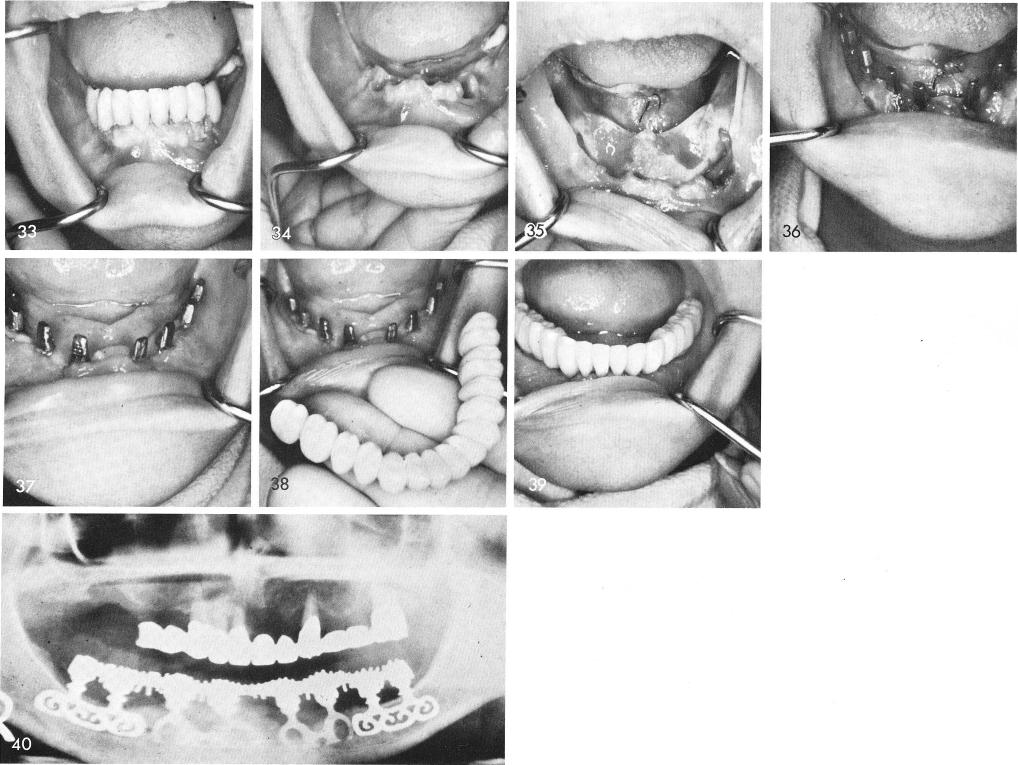

A severely periodontally involved mouth is seen in fig. 33. The remaining teeth were extracted, fig. 34, and the tissues were reflected and the sockets thoroughly enucleated of all granulation tissue, fig. 35. Notice also both mental nerve bundles. A double posted socket blade was inserted deeply into each socket to the left and right of the midline and regular type blades were inserted posteriorly, fig. 36. After sufficient healing of the soft tissues, fig. 37, the prosthesis was completed and cemented, figs. 38, 39. A post-operative x-ray, fig. 40.

1 Case involving severely periodontally involved mouth